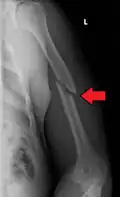

| Midshaft humerus fracture with callus formation | |